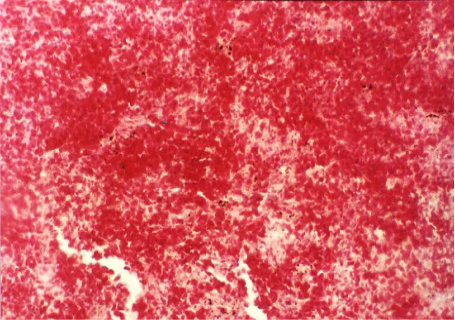

Figure 8

Hemorrhages in the spleen (H&E x 200)